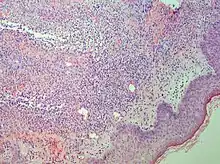

| Urticaria, lymphocyte predominant | Perivascular location. Mast cells are relatively sparse, potentially demonstrated with special stains, preferably tryptase stain. Extravasated erythrocytes are present in about 50% of the cases. No vasculitis.[14] | Dermal edema [solid arrows in (A,B)] and a sparse superficial predominantly perivascular and interstitial infiltrate of lymphocytes and eosinophils without signs of vasculitis (dashed arrow).[15] |

![]() |